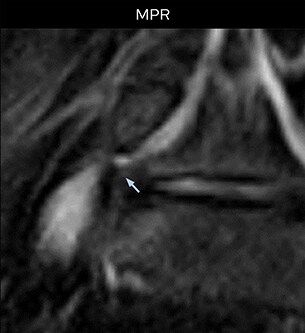

Clinical case: NerveVIEW shows right L5 radiculopathy and informs surgery

Low-grade glioma in a 5-year-old patient with neurofibromatosis 1. This low-grade lesion does not enhance on the post-contrast images, but does show an intermediate APT signal. The lesion stability over time confirms that it is a low-grade pathology. No abnormal findings were seen on routine MRI. Then x-ray radiculography was performed, but the contrast agent became trapped in transit and the nerve could not be fully observed. The peripheral nerve root is not contrasted in the nerve root block (x-ray radiculography) at the suspected location.

NerveVIEW images show that the spinal nerve is discontinued at the periphery of the dorsal root ganglion of the right L5 nerve root, suggesting nerve compression there. No other findings could explain the symptoms. With a diagnosis of extraforaminal herniation surgery was performed. Based on the findings using NerveVIEW, the surgeon decided to perform a hernia resection with a different, less invasive surgical approach from the outside of the multifidus muscle (B) instead of the usual approach (A). During surgery, disc herniation outside the intervertebral foramina was confirmed. Hernia resection released pressure on the nerve root and the right lower limb pain disappeared.

Impact of 3D NerveVIEW in this case

MRI on Achieva 3.0T dStream with NerveVIEW shows compression of nerve root outside the right L5/S1. Because NerveVIEW helped to accurately identify the location of the causative disease, a surgical approach could be chosen that prevented the need to peel off the muscle unnecessarily.

NerveVIEW shows right L5 radiculopathy and informs surgery

Clinical case: MRI of right L5 radiculopathy

In this patient with right hip to lower extremity pain, routine spine MRI at another hospital revealed L5/S1 disc herniation at the opposite side to the symptoms, but no abnormalities that could explain the patient’s chief complaint. At NFMC the patient underwent spine MRI with 3D NerveVIEW, because of a strong suspicion of L5 nerve root dysfunction based on the location of the painful area and symptoms related to sensory disorder. Achieva 3.0T dStream was used.